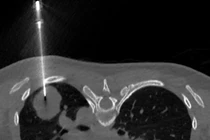

Người phụ nữ trẻ mắc ung thư phổi tế bào nuôi hiếm gặp Sức khoẻ 360 28/12/2025 13:02 Một ca bệnh hiếm gặp với u phổi ác tính hướng tới Choriocarcinoma, cho thấy tầm quan trọng của xét nghiệm và kiểm tra định kỳ trong chẩn đoán sớm.